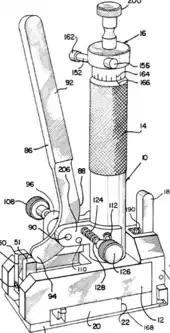

| Trocar |  |

Access instrument. Used to create an opening into a space without opening the abdominal cavity. A camera then inserted through one to view the inside of the space while instruments are inserted through the others to manipulate the organs. | |